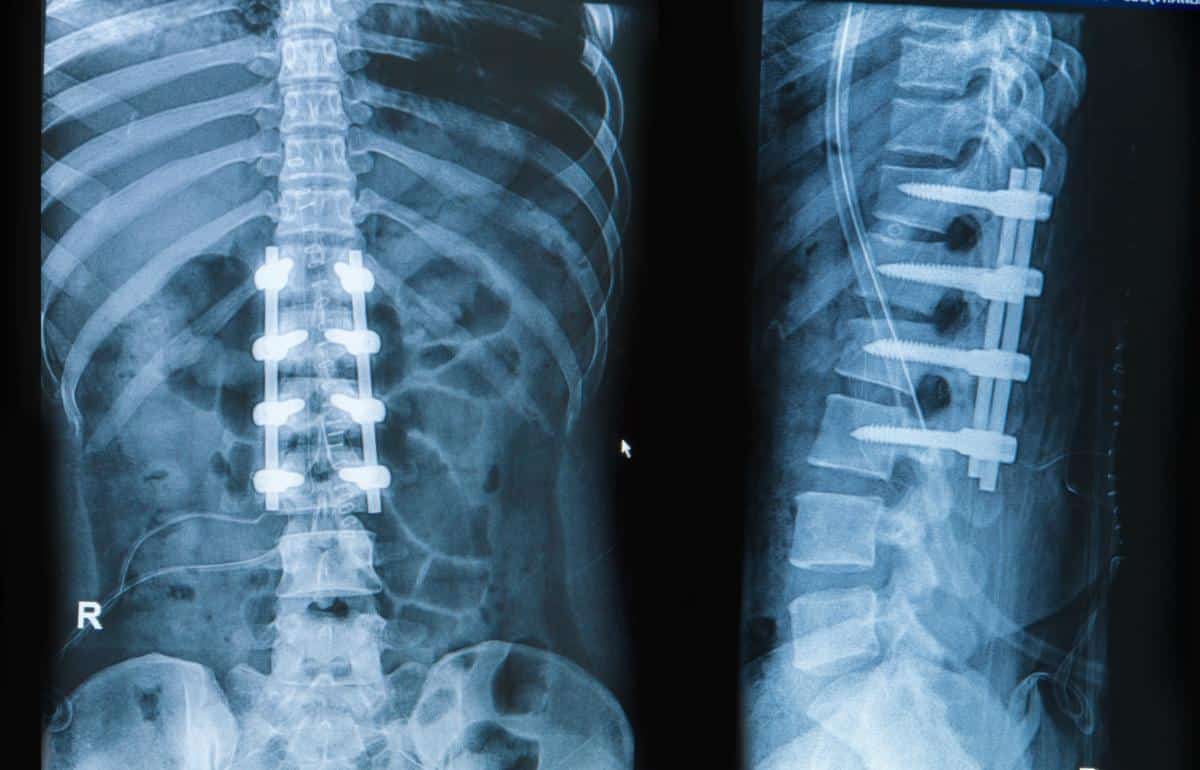

“(Spinal) Fusion is one of the most commonly performed spinal procedures, indicated for a wide range of spinal problems. Elimination of motion though results in accelerated degeneration of the adjacent level, known as adjacent level disease. Motion preservation surgical methods were developed in order to overcome this complication. These methods include total disc replacement, laminoplasty, interspinous implants and dynamic posterior stabilization systems. The initial enthusiasm about these methods was followed by certain concerns about their clinical usefulness and their results.”

In this study surgeons reassessed a few of the most commonly performed spinal fusion alternative surgical procedures. “(Motion preservation surgical methods) include total disc replacement, laminoplasty (cutting away of bone and other pressure causing material on the nerves), interspinous implants (spacers to hold nerve pathways open) and dynamic posterior stabilization systems (not a fusion but similar).”

“Spinal fusion is the most widely accepted treatment for lumbar disc degenerative disease. However, it has been associated with adjacent segment degeneration as a potential long-term sequel especially in those with preoperative risk factors, which may cause aberrant stress forces in these segments and lead to adjacent level degeneration. (The fixation at certain spinal levels now shifts the and creates new pressure patterns on the next available segment that has not been fused causing problems that joint.) Adjacent segment pathology can include adjacent segment degeneration and adjacent segment disease, although a clear and consensual definition of adjacent segment disease is missing. In most studies, adjacent segment degeneration is defined as radiographic changes in the intervertebral discs adjacent to the surgically treated levels, whereas adjacent segment disease is defined as the pathologic process associated with disc degeneration leading to clinical symptoms, such as radiculopathy, stenosis and instability. Nevertheless, there are a few reports considering reoperation rate as being the most reliable parameter to define adjacent segment disease, despite clinical symptoms.”

While they appear to be realistic surgical options for a complicated spinal problem, the initial enthusiasm about fusion surgery was followed by certain concerns about their clinical usefulness and their results.